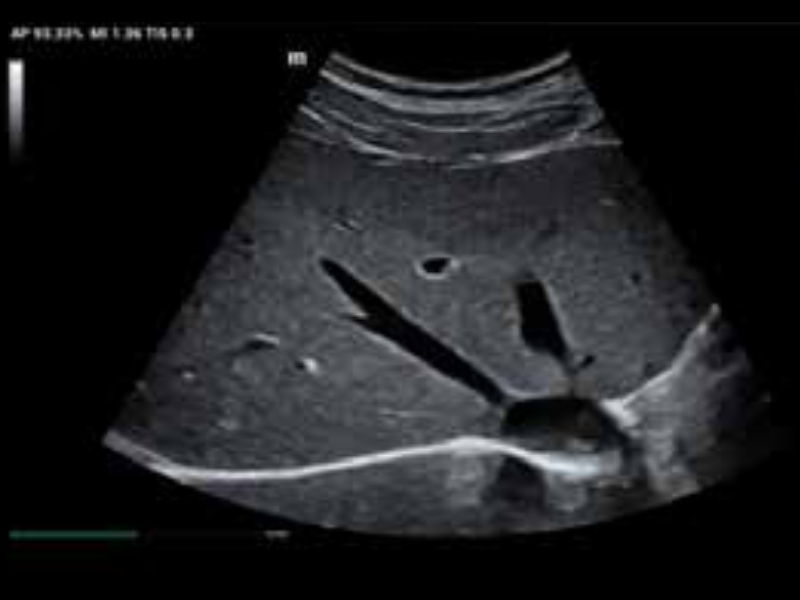

• zeus-fig5-1-1-uk

Wątroba w trybie B. Platforma ZST+ z dynamicznym ogniskowaniem na pikselach